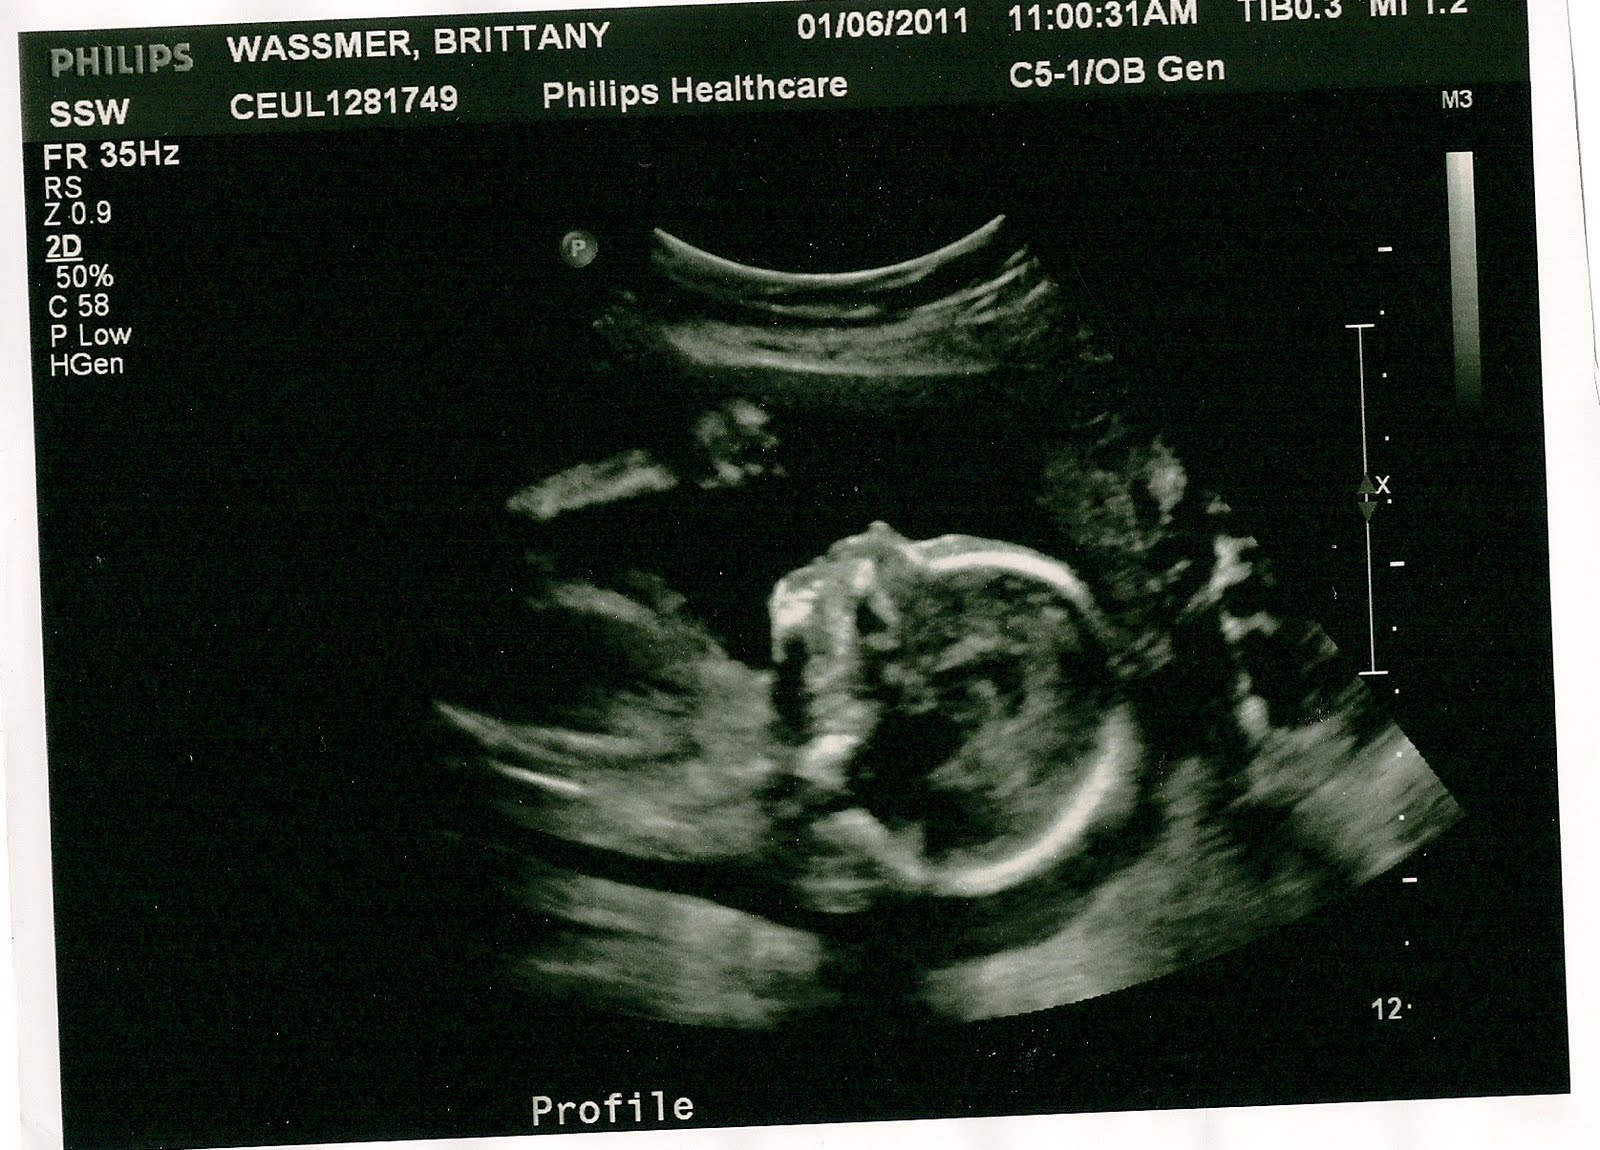

Well, a lot has happened since last Fall. I am currently 26 weeks pregnant with our little girl! Ryan is going to have a sister! The ultrasounds show she is growing well and all looks good from our end. My official due date is May 29, but Tom has his heart set on June 3. We'll see! Below are some pics of our little girl that I received free as a volunteer for Alternatives Pregnancy Center.